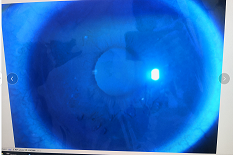

完成期:發(fā)展迅速,角膜明顯前突,視力銳減。

瘢痕期:角膜急性角膜水腫、混濁,消退后基質(zhì)層殘留瘢痕。